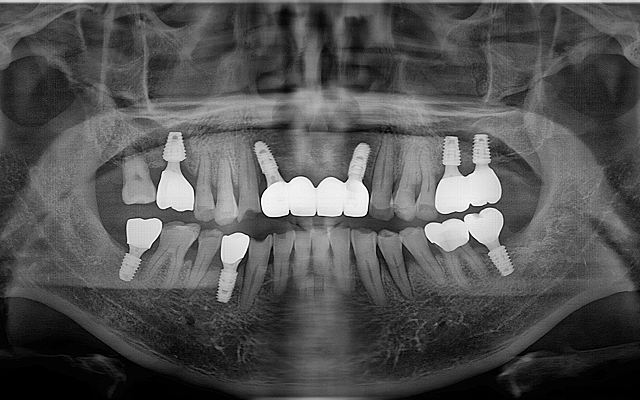

전악 케이스

- 상·하악 전체 보철 설계를 통해 정확한 교합(물림) 회복

- 심미·발음·저작 기능을 종합 고려한 자연스러운 전악 임플란트